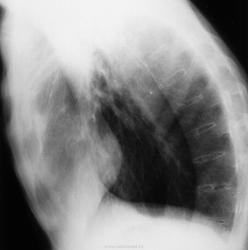

Бродил я, в очередной раз, по всевозможным обучающим ресурсам. Наткнулся на представленные картинки, подумал – «старый тубер» и, по всей видимости, как исход двустороннего фиброзно-кавернозного. Однако, все оказалось намного интереснее. Статья группы авторов (из буржуйских) была посвящена легочным проявлениям системных аутоиммунных заболеваний. Много интересного, из той статьи, я уже разместил на сайте «по темам» (ревматоидное лёгкое и др.). Эти картинки были озаглавлены, как «лёгочные проявления» при болезни Бехтерева.

Так ведь анкилозирующий спондилоартрит, более известный публике как болезнь Бехтерева виден тут в своей III ст. невооружённым глазом. Так что путь мой был недолгим. А что, в этом случае причастность туберкулёза к пневмоциррозу буржуины отрицают полностью? И гарантируют? — со своей стороны интересуюсь я.

При болезни Бехтерева обнаруживаются избирательные поражения внесуставных тканей. Возможно развитие двустороннего верхушечного легочного фиброза и образование полостей, напоминающих туберкулез. В наблюдении В.Л.Катенёва, представленные изменения могут не иметь связи с туберкулёзом. Известно, что наряду с уменьшением гибкости позвоночника ограничивается подвижность суставов, связывающих ребра с грудными позвонками. Это приводит к нарушению дыхательных движений и ослаблению вентиляции легких, что может способствовать возникновению хронических легочных заболеваний. Следует поблагодарить автора за очень важную тему, которая расширяет кругозор врачей. С уважением Nik.